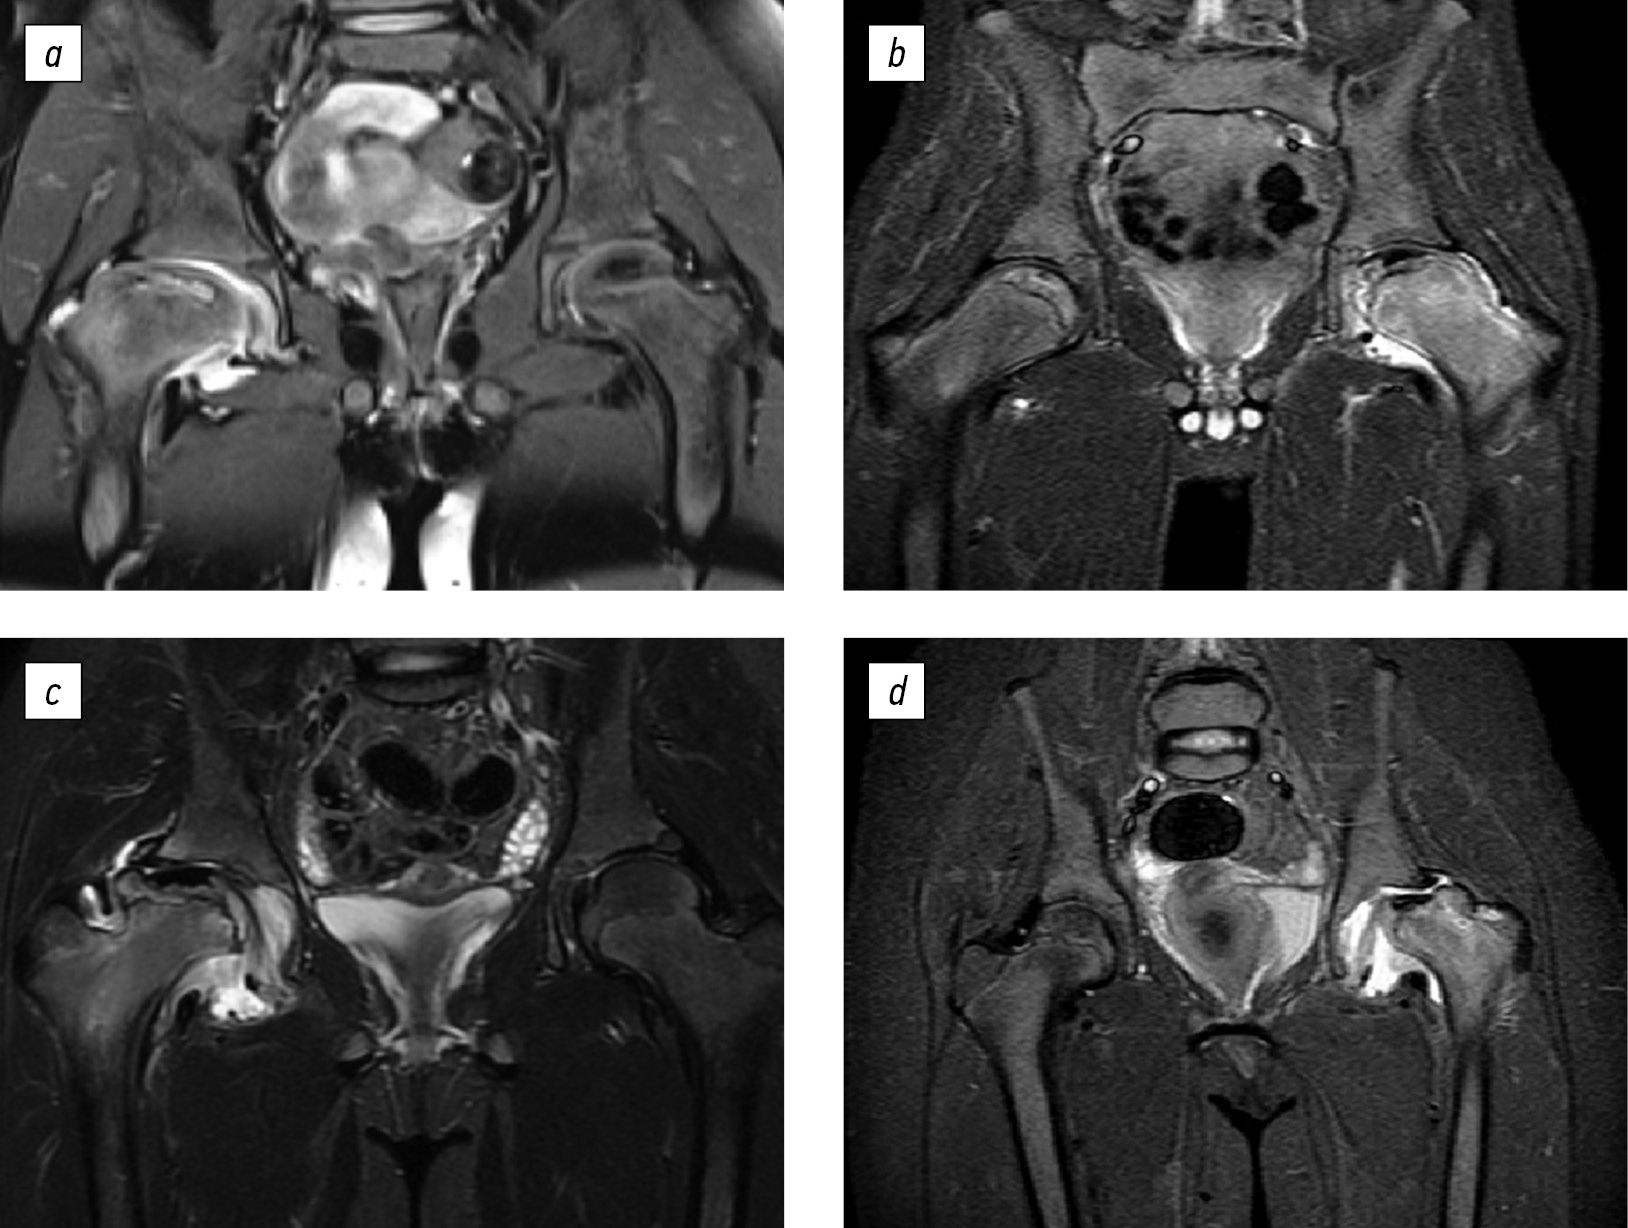

Use of bisphosphonates in pediatric patients with Legg–Calvé–Perthes disease

Studies examining the efficiency of bisphosphonates in pediatric patients with ANFH are scarce. Clinical data supporting the use of bisphosphonates in juvenile forms of osteonecrosis are limited and should be critically evaluated [45]. A database search revealed a need for more information on the effectiveness of bisphosphonates in pediatric patients with ANFH, including LCPD. We examined proposed solutions to optimize therapy for osteoarthritis in pediatric patients with LCPD. An analysis of a series of patients treated at H. Turner National Medical Research Center for Children’s Orthopedics and Trauma Surgery indicated that in LCPD with signs of a pronounced inflammatory process in the early stages of the disease, the volume of the necrosis focus often increased, and extrusion subluxation developed in the affected joint. Additionally, synovitis hindered timely conservative and surgical treatment. Without proper treatment, this disease variant inevitably ended in the formation of gross deformity of the articular components (Fig. 4). Similar conclusions regarding the negative impact of chronic synovitis on the disease course were made in English-language studies [46]. Currently, in the treatment of pediatric patients with LCPD, previously developed schemes are traditionally used in the form of conservative measures using abduction orthoses and plaster casts, as well as surgical interventions, namely, triple pelvic osteotomy, Salter pelvic osteotomy, varus femoral osteotomy. The listed treatment methods, included in the concept of containment therapy, are based on the complete “immersion” of the femoral head into the acetabulum, which is necessary to prevent the head deformity progression and improve its shape, as well as restore the congruence of the articular surfaces. However, this treatment option cannot positively affect the hyperactivity of osteoclasts in the area of necrosis, including the course of osteoarthritis [47, 48]. Consequently, numerous studies have been aimed at finding a drug therapy model that would reduce inflammation and osteoclast activity, preventing the progression of head deformity, and restoring its sphericity [49].

Fig. 4. A series of magnetic resonance imaging in pediatric patients with LCPD with signs of osteoarthritis: (a, b) without subluxation in the affected joint; (c, d) with subluxation of the femoral head (from the author’s archive)